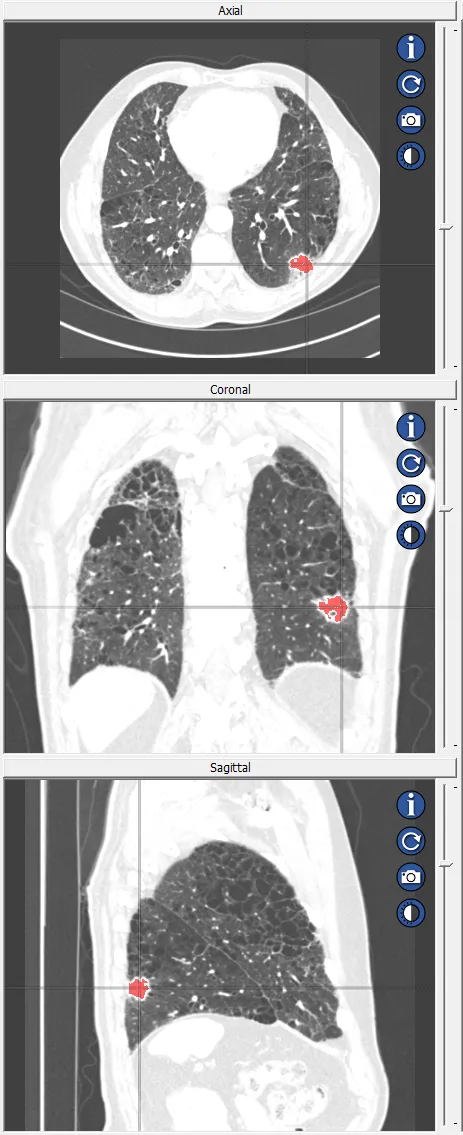

See Segmentation for Pro Surgical 3D in action!

Basic Segmentation Tools:

Manual, Automatic, and Threshold